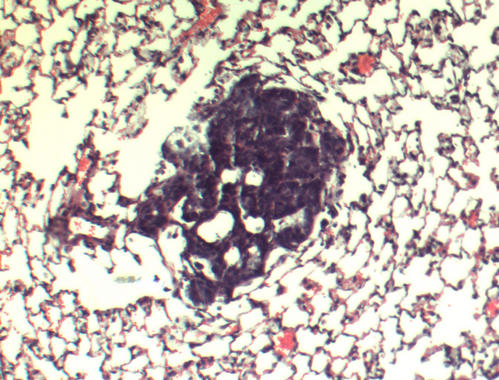

El colesterol alto acciona el crecimiento del cáncer de mama 29/11/2013Científicos de la Universidad de Duke (Carolina del Norte, EE.UU.) han liderado un estudio sobre la influencia del colesterol en el riesgo de cáncer de mama. Los resultados, aún preliminares, se publicaron ayer en la revista Science. El trabajo, realizado en ratones, explica por primera vez esta relación, especialmente en mujeres posmenopáusicas,. "Una gran cantidad de estudios ya demostraron una relación entre obesidad, en concreto entre el colesterol elevado, y cáncer de mama, pero hasta ahora no había sido identificado ningún mecanismo que lo explicara", apunta Donald McDonnell, director del departamento de Farmacología y Biología del Cáncer en Duke y autor principal del estudio. El experto explica que lo que su equipo ha encontrado es una molécula –un metabolito abundante del colesterol– denominada 27HC que imita al estrógeno y puede accionar de forma independiente el crecimiento del cáncer de mama. “El hallazgo de que el colesterol elevado (y 27HC) acorta drásticamente en animales el tiempo para sufrir cáncer realmente nos llamó la atención”, indica a SINC McDonnell. La hormona estrógeno alimenta alrededor de un 75% de todos los cánceres de mama. En estudios anteriores del laboratorio de McDonnell, los investigadores determinaron que el 27HC se comporta de manera similar a los estrógenos en los animales. Para su trabajo actual, los investigadores se propusieron determinar si esta actividad del estrógeno era suficiente por sí misma para promover el crecimiento del cáncer de mama y metástasis, y si su control tendría un efecto contrario. “Observamos que la actividad de este metabolito del colesterol fue inhibida cuando los animales fueron tratados con antiestrógenos, o cuando se interrumpió la administración de suplementos de 27HC”, subraya McDonnell. Tras probarlo en ratones, los estudios fueron corroborados en tejido de cáncer de mama humano. Más información SINC